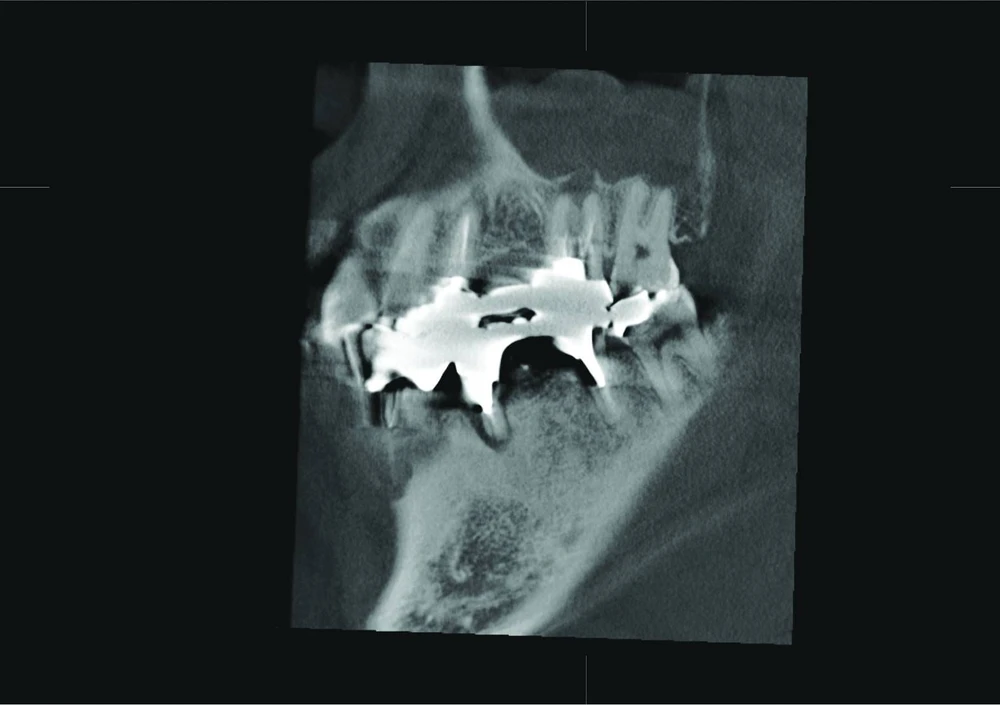

The patient presented with an unclear situation around tooth 26, which had undergone endodontic treatment before. Conventional 2D X-rays did not allow a conclusive diagnosis; therefore, a 3D scan was performed with Veraviewepocs 3D R100. The sagittal and coronal view showed that the endodontic treatment had not been successful and that there were apical defects on the buccal and palatal root.

The sagittal view clearly confirms perforation of the Schneiderian membrane, and the coronal view revealed an odontogenic maxillary sinusitis and pachymenia. The injury of the sinus membrane may have been overlooked in this case if the diagnosis had been formulated on the basis of an X-ray that did not show the problem so clearly.